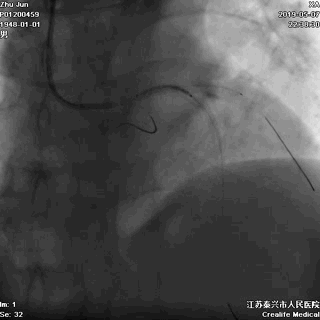

非顺应性球囊高压后扩,保证STENT充分贴壁

大一号球囊高压扩张近段STENT

手术即刻效果完美,患者存活